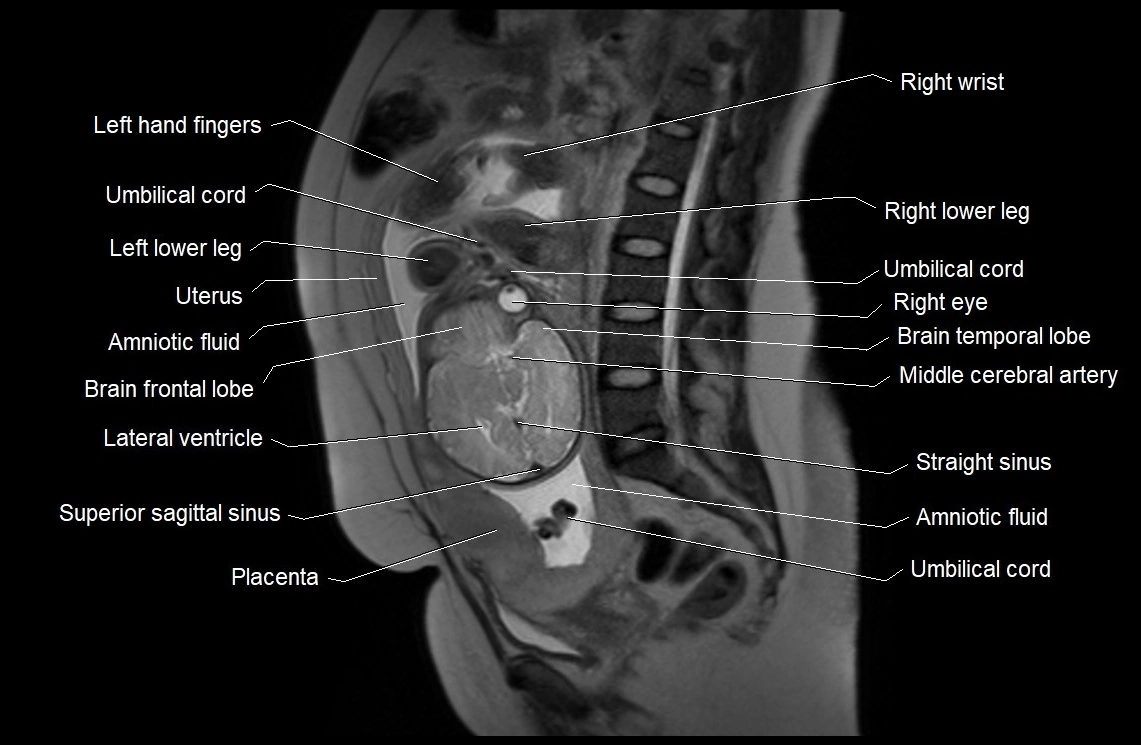

MRI Appearance

T2 HASTE (T2 GRE):

• Amniotic fluid shows very bright hyperintense signal

• Provides natural contrast against fetus and placenta

• Small particles (vernix) may appear as scattered hypointense foci within bright fluid

MRI image

image